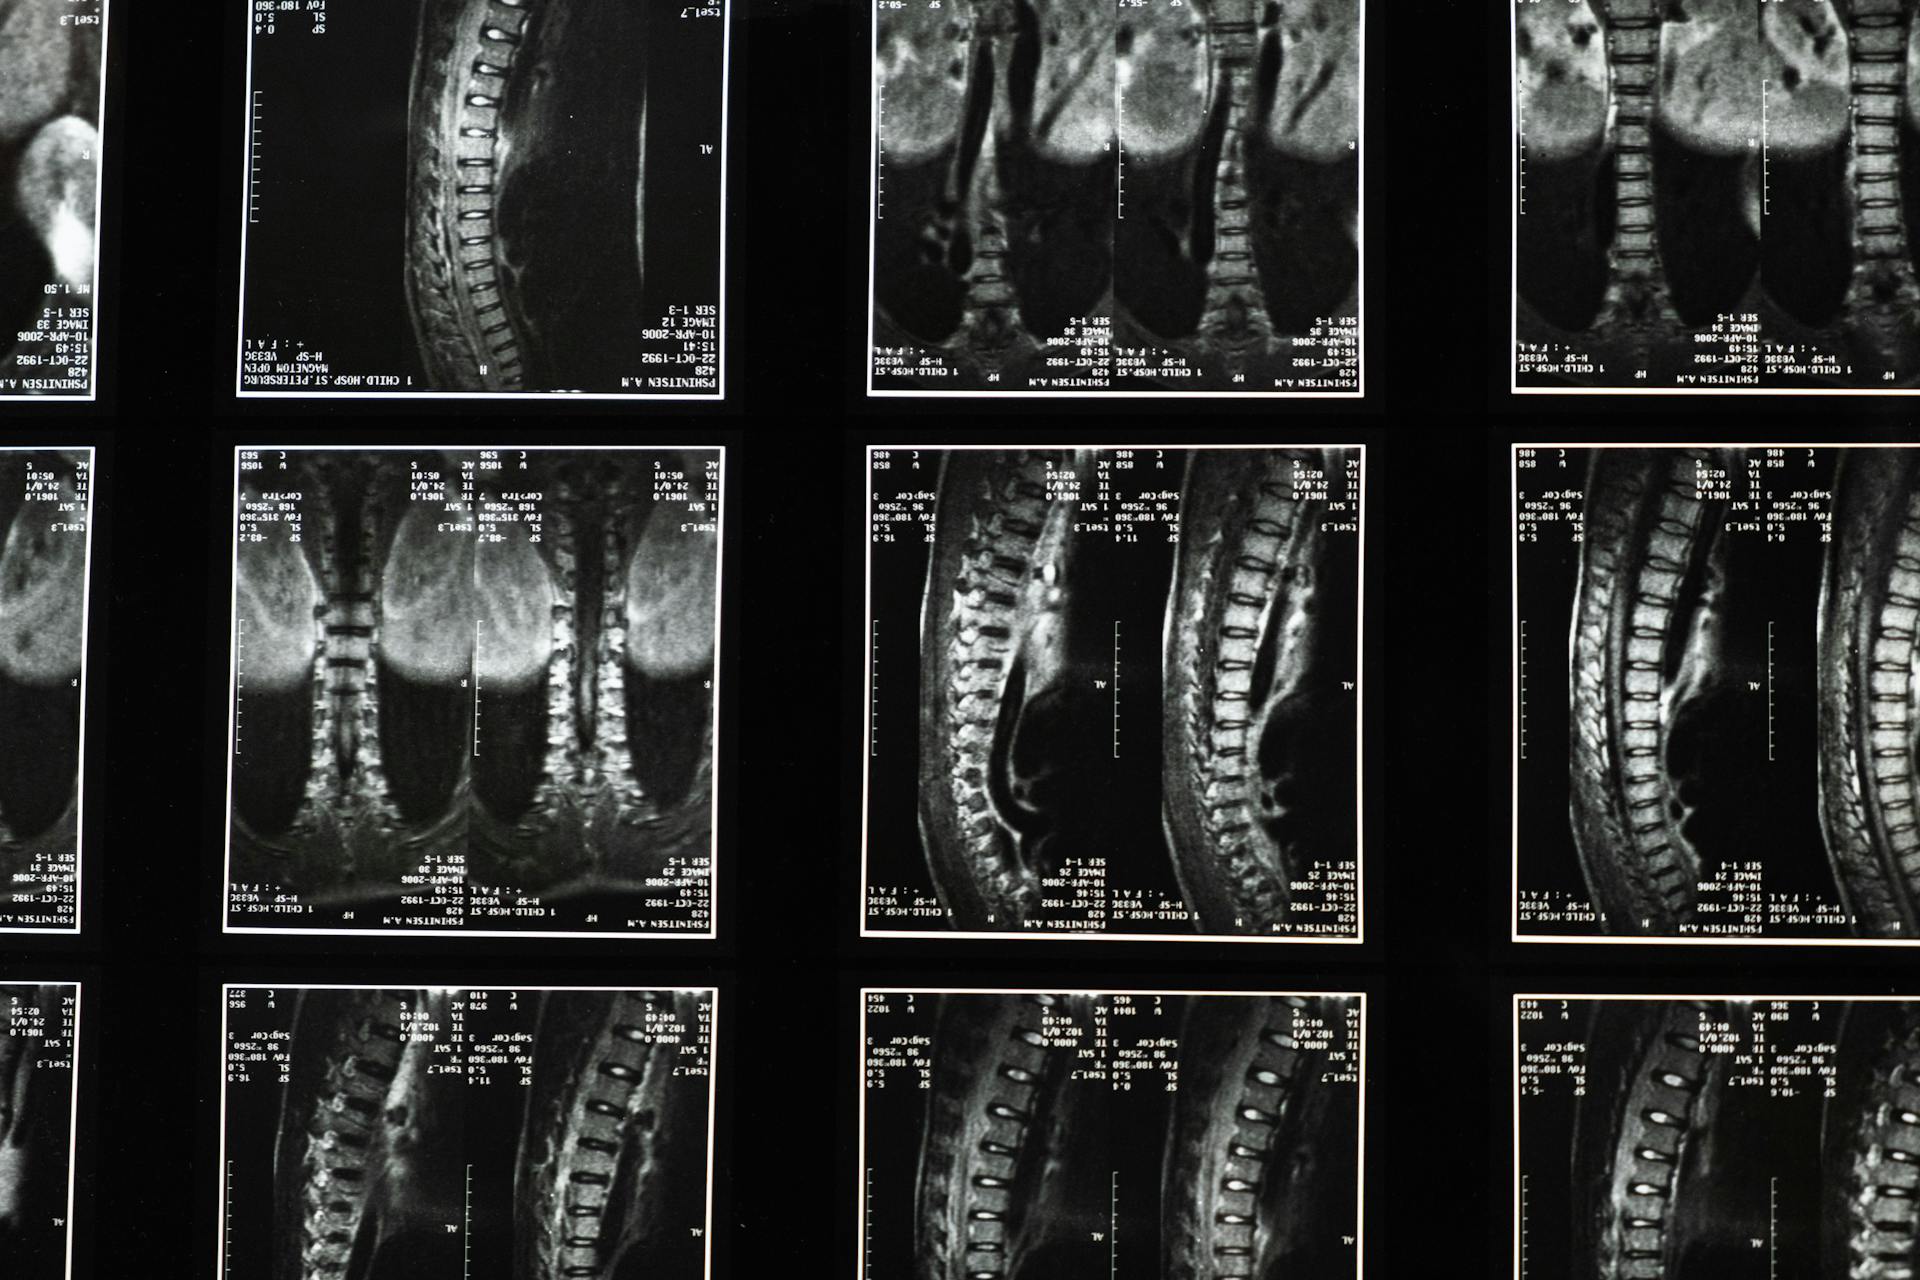

Common Conditions Treated by our Providers

Herniated Discs

When a spinal disc shifts or ruptures, it can press on nearby nerves, causing persistent pain, numbness, tingling, or weakness that affects daily movement.

Spinal Stenosis

When the spinal canal gradually narrows, it can compress nearby nerves, leading to ongoing pain, stiffness, numbness, and difficulty with walking, standing, or everyday movement.

Sciatica & Radiculopathy

When spinal nerves become irritated or compressed, it can result in radiating pain, numbness, tingling, or weakness that may affect the legs, arms, or daily activities.

Ultra Minimally Invasive Endoscopic surgery is the new standard. By utilizing advanced cameras and instruments through a keyhole incision, we treat conditions like herniated discs and stenosis with unmatched precision, preserving surrounding muscles and accelerating healing.